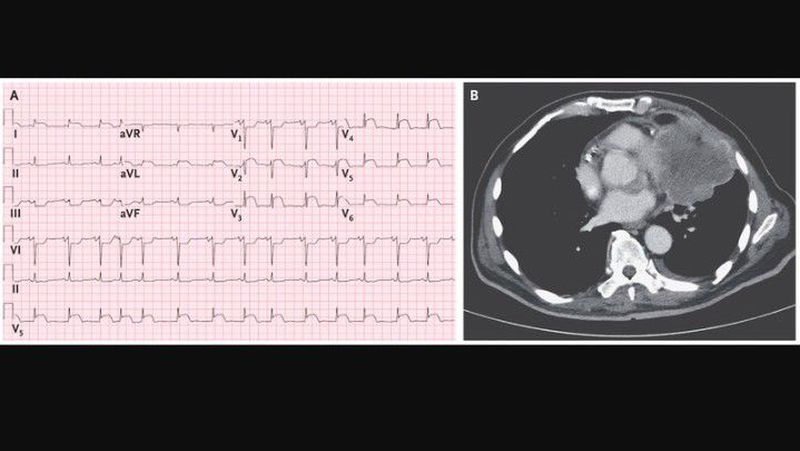

An 84-year-old man presented to the emergency department with generalized weakness and shortness of breath. Electrocardiographic results aroused concern that he had an ST-segment elevation myocardial infarction (STEMI), and the patient was transferred to a hospital that had a cardiac catheterization laboratory. On arrival at the second hospital, the patient had no chest pain. An electrocardiogram showed ST-segment elevation in leads I, aVL, and V2 through V6(Panel A). The troponin I level was 0.15 ng per milliliter (reference value, <0.03). On further discussion with the patient and review of the records, it was discovered that the patient had been hospitalized 1 month earlier because of unintentional weight loss. Computed tomography (CT) of the chest at that time revealed a large intrathoracic mass invading the left ventricle (Panel B). CT-guided needle biopsy during that hospitalization revealed poorly differentiated non–small-cell carcinoma. An electrocardiogram during that hospitalization showed ST-segment elevations in a similar pattern, but they had become more prominent by the time of the second admission. This pattern was thought to be due to tumor invasion of the myocardium, and coronary angiography was not performed. After a discussion of treatment options with the patient and his family, the decision was made not to pursue surgery or chemotherapy. Goals of care were transitioned to focus on the patient’s comfort, and he died several days later.